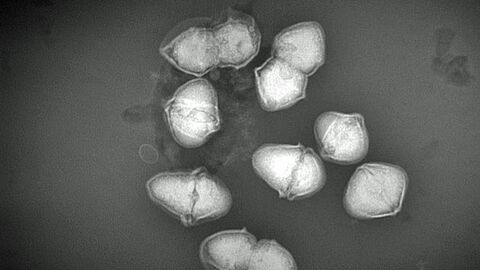

Speziesbeschreibungen sind wissenschaftlich aufwändig, da eine Vielzahl an Eigenschaften und Daten über das Bakterium zusammengetragen werden müssen. Dies wurde nur durch die gute und vertrauensvolle Zusammenarbeit der beteiligten Institutionen möglich, zu der auch Experten aus zwei Instituten der Justus-Liebig-Universität Gießen, dem Robert-Koch-Institut in Berlin und dem Nationalen Referenzzentrum für Streptokokken am Universitätsklinikum Aachen gehörten. Wie bereits mehrfach in den letzten Jahren ergänzte die Expertise des CVUA Stuttgart in der identifizierenden Spektroskopie und der Elektronenmikroskopie die Arbeiten an den Streptokokken der Zootiere [Abbildung 3].

Elektronenmikroskopische Abbildung des neu beschriebenen Bakteriums Streptococcus catagoni

Abb. 3: Elektronenmikroskopische Abbildung des neu beschriebenen Bakteriums Streptococcus catagoni